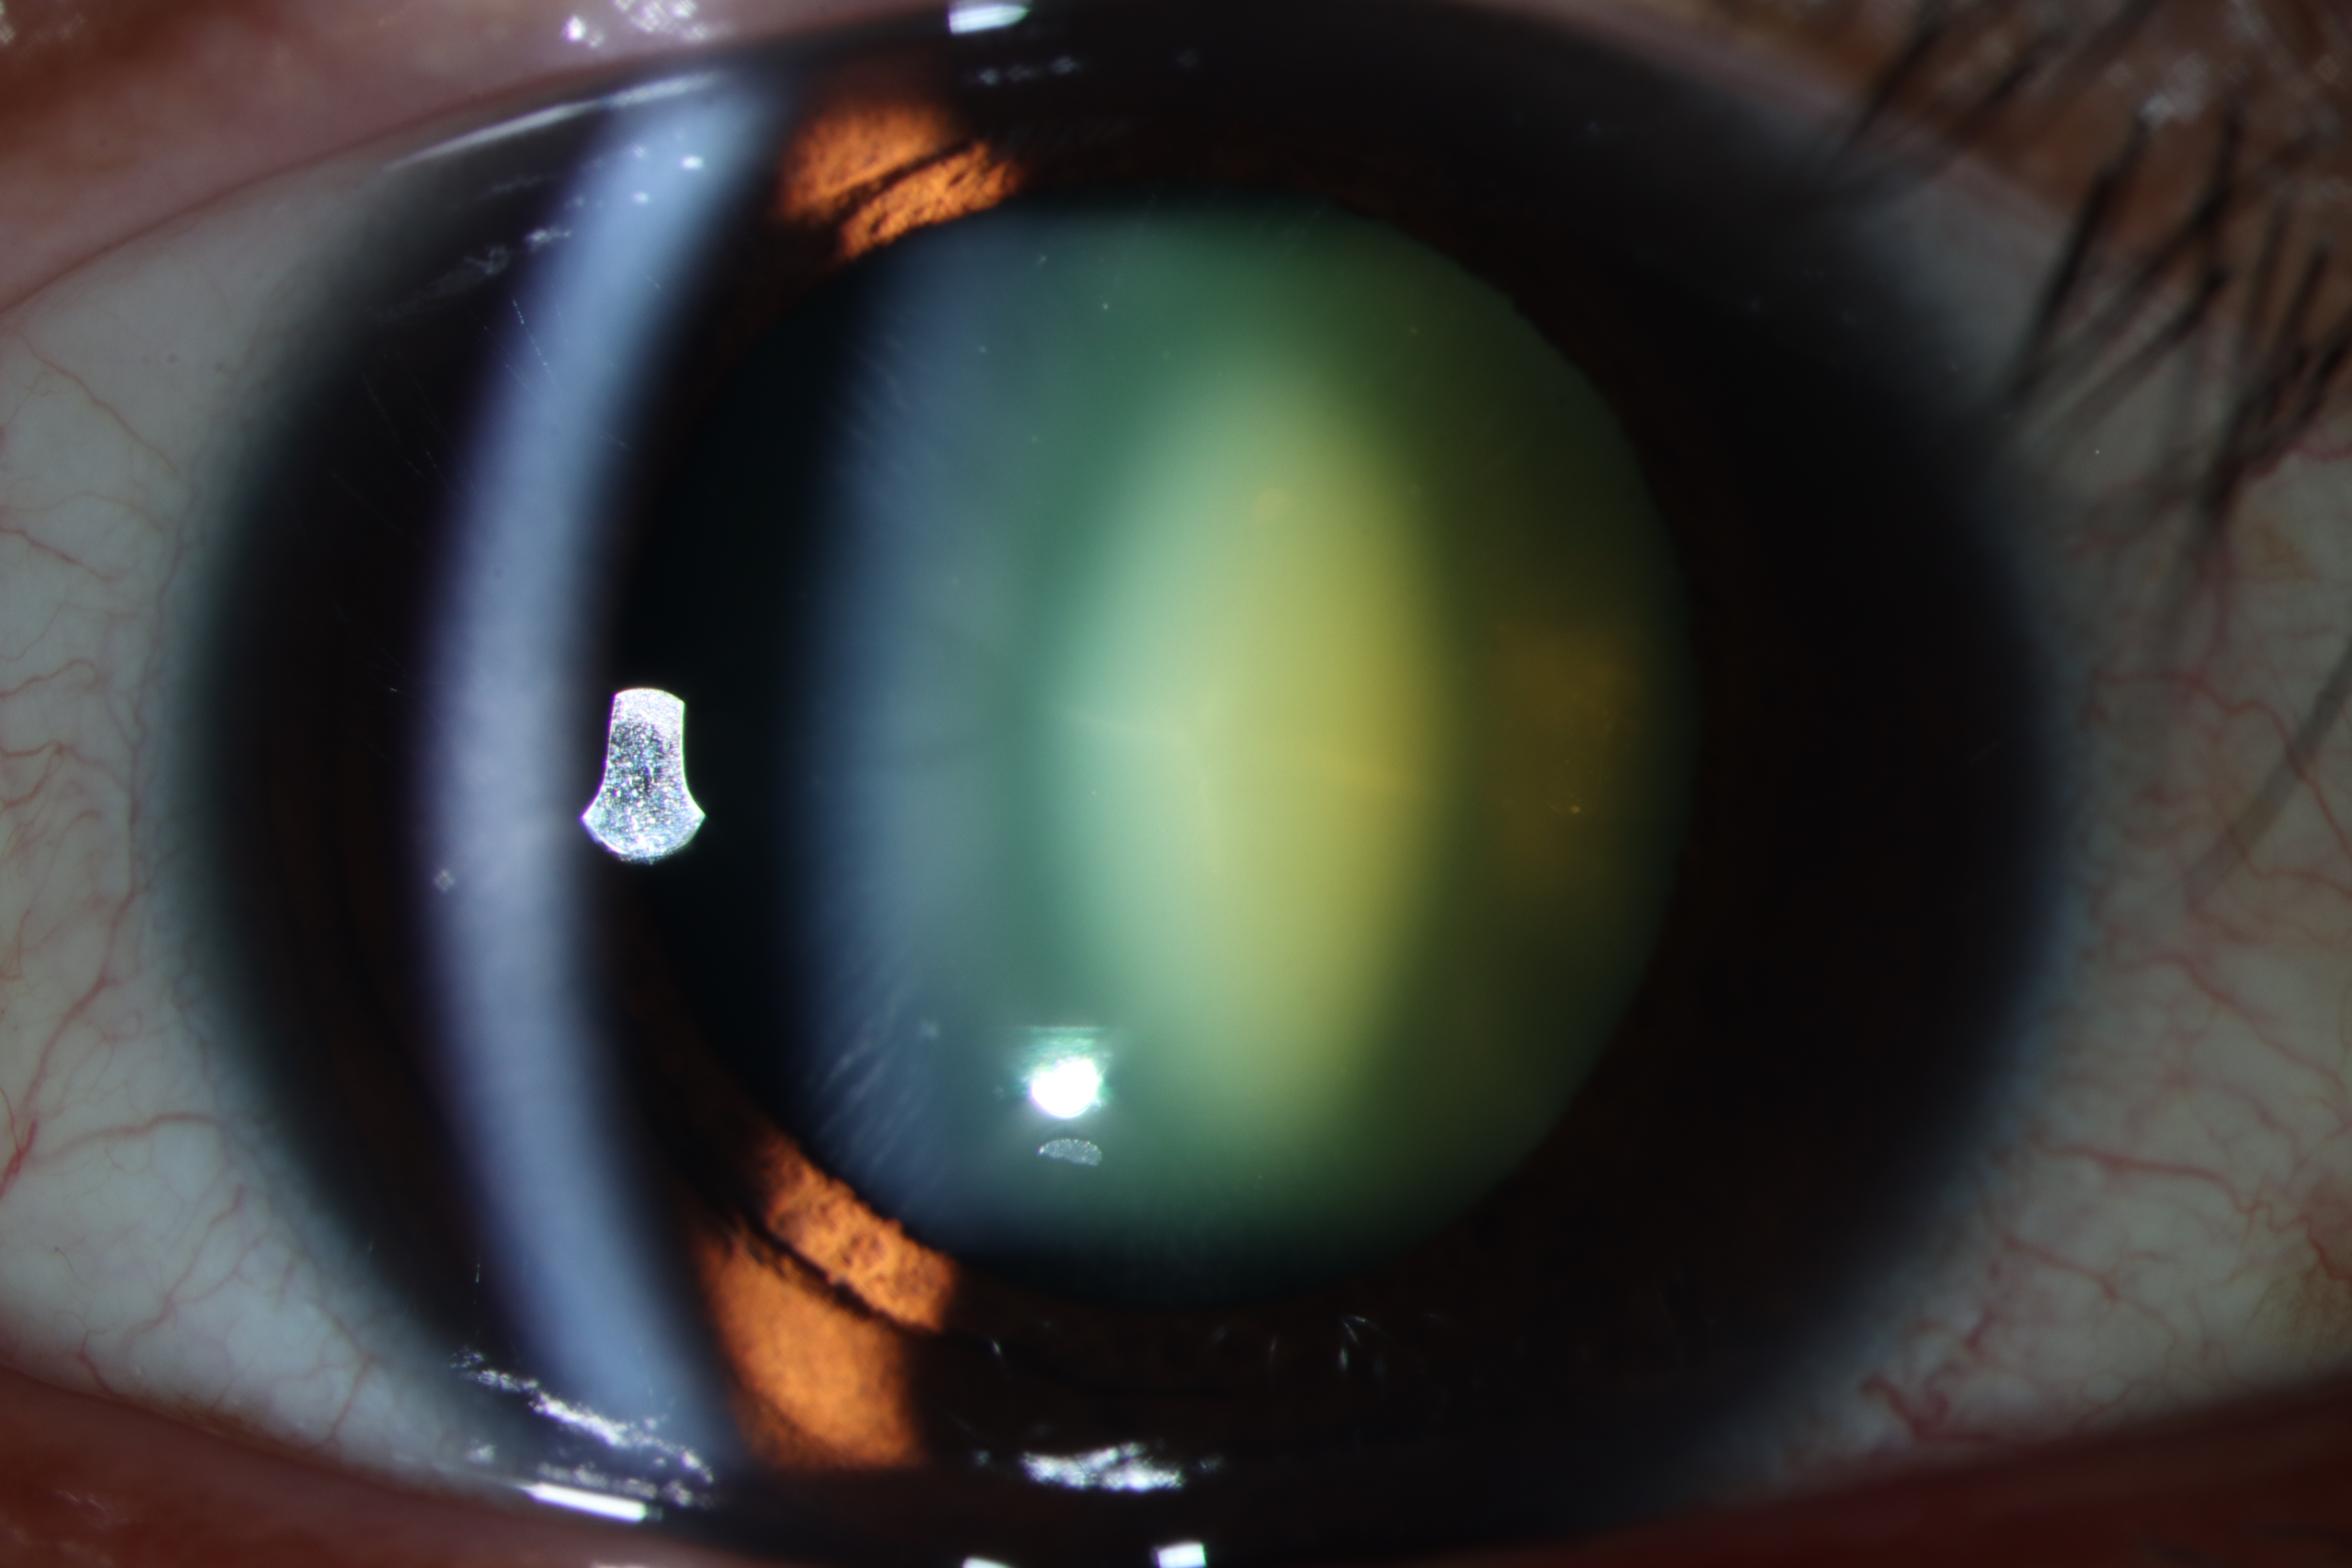

Diffuse illumination slit lamp photograph of an oil-droplet cataract showing central nuclear yellow opacity of the lens with dark clearing surrounding the oil-droplet.

Optical section slit lamp photograph of the right eye showing a 3+ oil-droplet cataract with the central yellow opacified nucleus surrounded by an area of dark clearing followed by the cortical and capsular layers anteriorly.